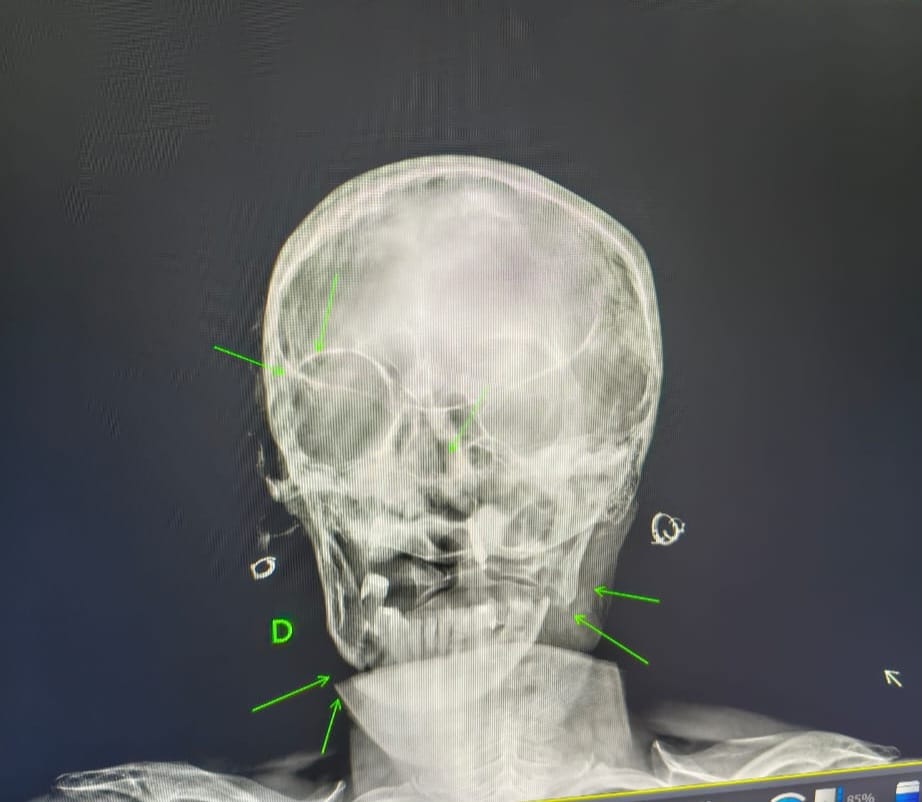

Segundo informações, o agressor — filho da vítima — iniciou ataques com socos e pauladas após uma discussão, chegando a agredir também o irmão que tentou intervir. A mãe sofreu fraturas na mandíbula, nariz e clavícula, sendo encaminhada ao hospital municipal e posteriormente transferida para a UTI da Santa Casa de São Carlos.